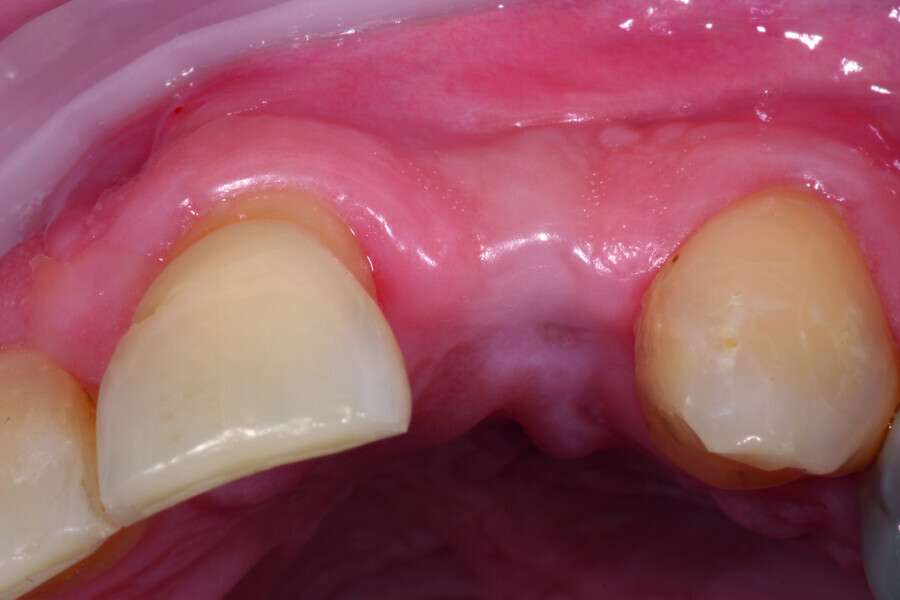

Digitising your implant practice